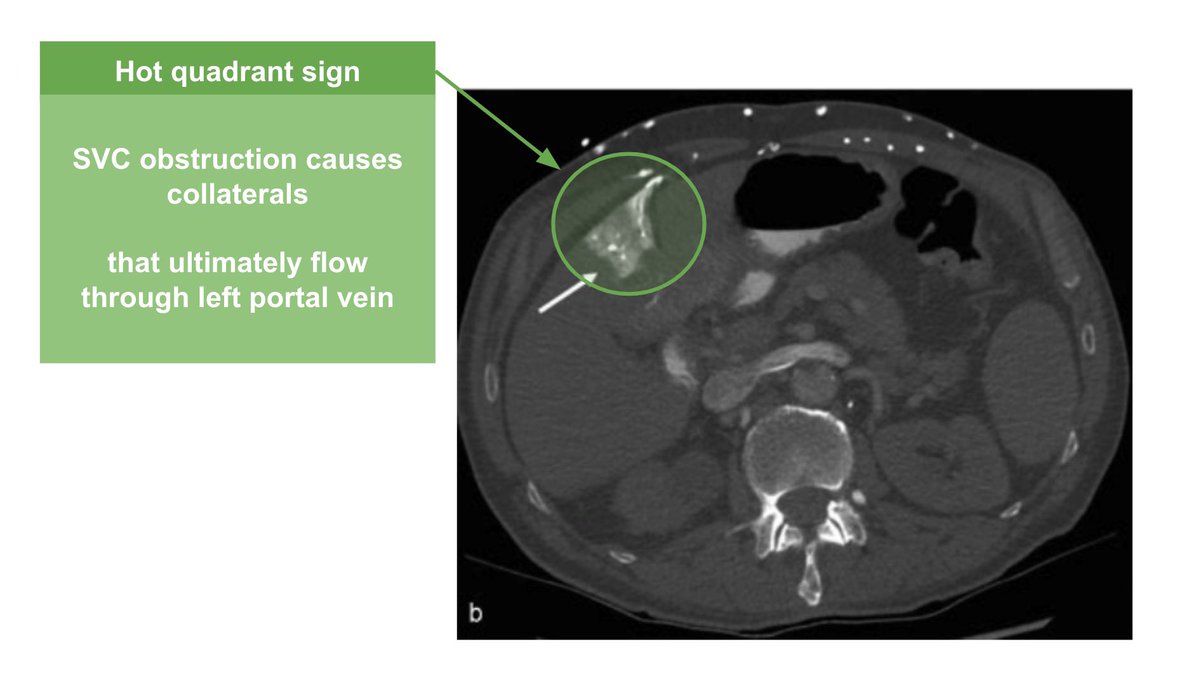

Picture this: A patient is found unconscious at home, and you find this ๐Ÿ‘‡ on your evaluation. Why (and how) is this an emergency? ๐Ÿค” ๐Ÿงต 1/8